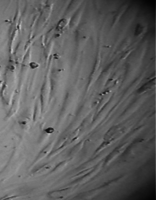

Клетки культивировали в стандартных условиях в термостате Sanyo – Incubator MIR-262 при температуре 37°С в среде МЕМ с 10% эмбриональной телячьей сыворотки в пластиковых культуральных флаконах Orange Scientific (производство Бельгии), Corning (производство США) площадью 25 и 75 кв. см. Тестирование производили в культуральных чашках Петри Sarstedt диаметром 3 см (рис. 3).

Ежедневно проводили визуальные наблюдения и морфометрию нативной культуры.

Визуально оценивали целостность монослоя, наличие слущенных клеток в культуральной жидкости, форму и размеры клеток, структуру клеток (состояние цитолеммы, состояние цитоплазмы – наличие вакуолей, зернистости, наличие и состояние отростков, структуру ядра и ядрышек, положение ядра в клетке, количество ядер и ядрышек в клетках).

Вид монослоя и структура клеток не отличались от обычных в течение всех четырех суток наблюдения (рис. 32).